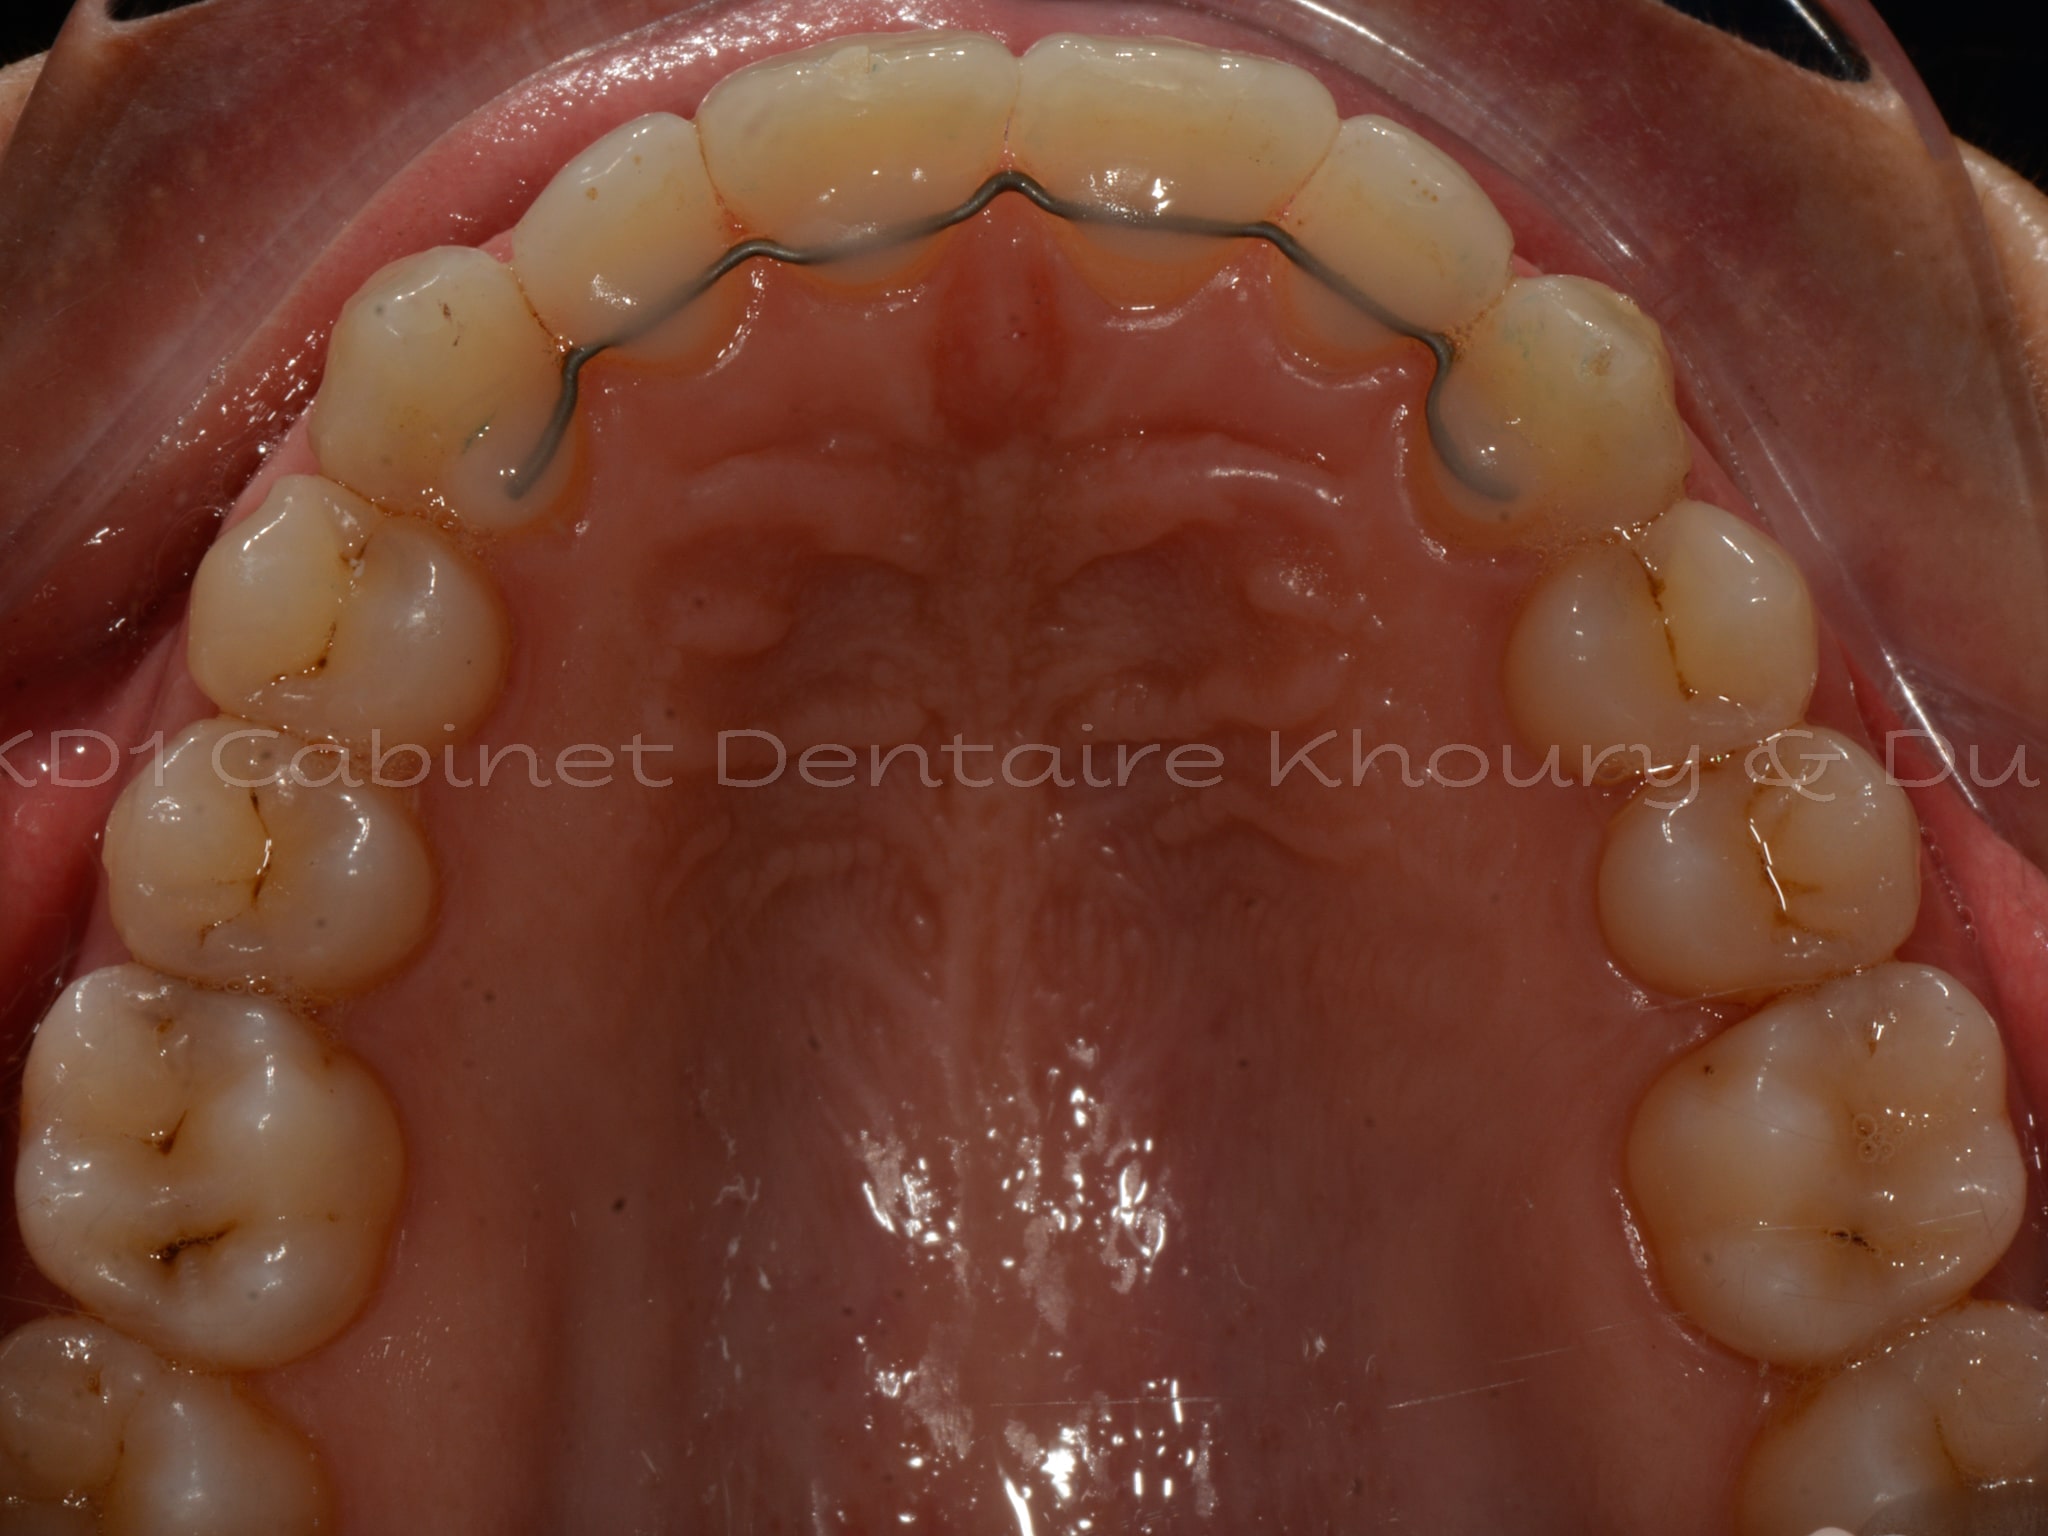

Cas #1 – Traitement avec des bagues, deuxièmes prémolaires et dent de sagesse supérieures ectopiques.